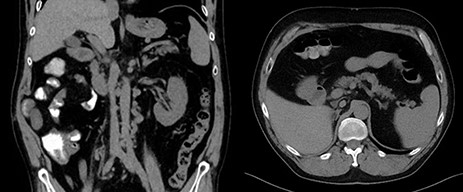

The detailed histopathology revealed a tumor of 10-cm maximum diameter, clear cell, with extensive areas of hemorrhage and necrosis, no evidence of lymphovascular invasion and no rhabdoid or sarcomatoid differentiation, negative surgical margins. The IVC thrombus was all formed of necrotic tissues with no active malignancy. Patient was decided to continue on Sutent after the recovery of surgery. One year follow-up showed no tumor recurrence and normal IVC without thrombus (Fig. 2).

Post-operative coronal and axial CT images showing free tumor bed and normal IVC.